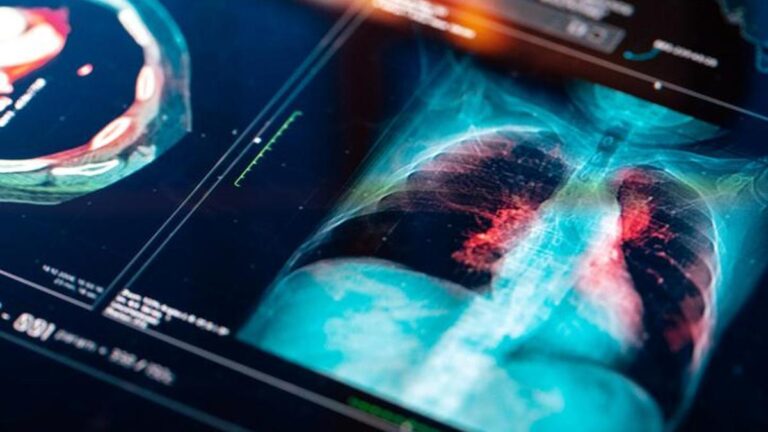

Akciğer Kanseri Belirtileri Nelerdir? Akciğer Kanseri Nasıl Anlaşılır? Tedavi Yöntemleri Nelerdir?

Bu nedenle, düşük dozaj akciğer tomografisinin bu anlamda önemli bir yeri vardır. Özellikle erken tomografi ile gerekli tedavi yöntemleri daha etkili olabilir. Ek olarak, kan testleri ve açıklık testleri de pulmoner kanser açısından tartışılmaktadır. Bu nedenle, gerekli tanılarda tartışılan yöntemler birden fazla şekilde kullanılır ve sonuç dahil edilir.